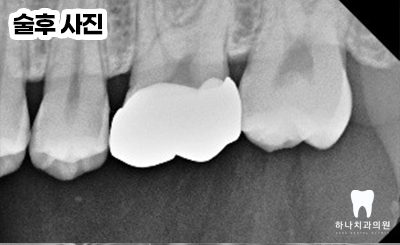

모든 치료를 마치고 난 후,

4년 뒤에도 전혀 문제를 발견할 수

없었고 주변 자연 치질과 조화로운 잇몸

기능을 유지하고 있는 것을 관찰하였습니다.